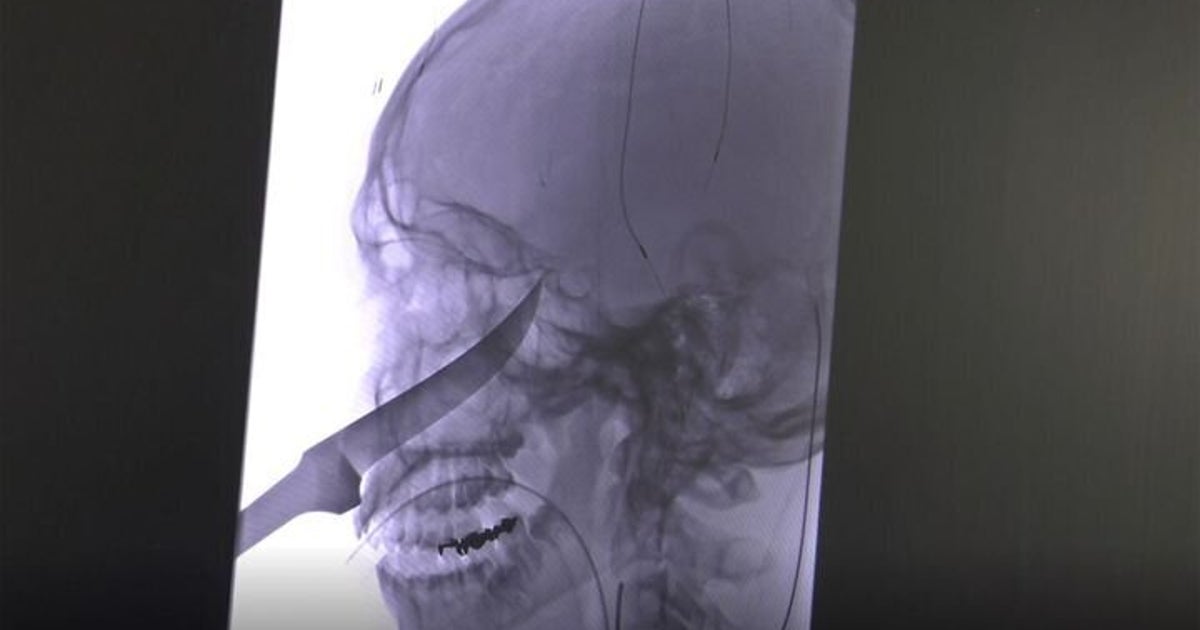

顔に25センチのナイフが刺さった少年 奇跡的に一命を取り止める ハフポスト